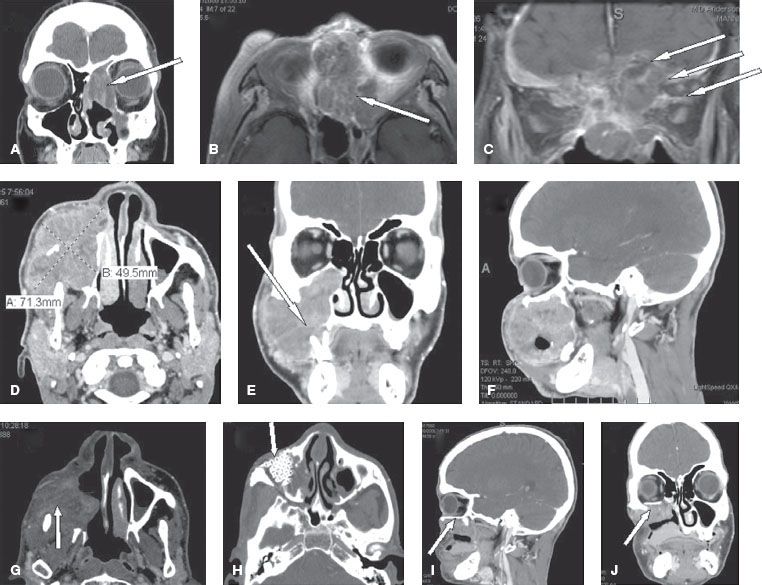

Cancer of the Nasal Cavity and Paranasal Sinuses Oncohema Key Can Mold Cause Sinus Cancer Yet the effects of mold are often misdiagnosed, undiagnosed, or left. There are several types of. Aspergillus can invade areas of your body other than your lungs, such as your sinuses. In most cases, nasal cavity and paranasal sinus cancers are found because of problems they cause. Finding these cancers in people without. Mold exposure symptoms can be combated if. Can Mold Cause Sinus Cancer.